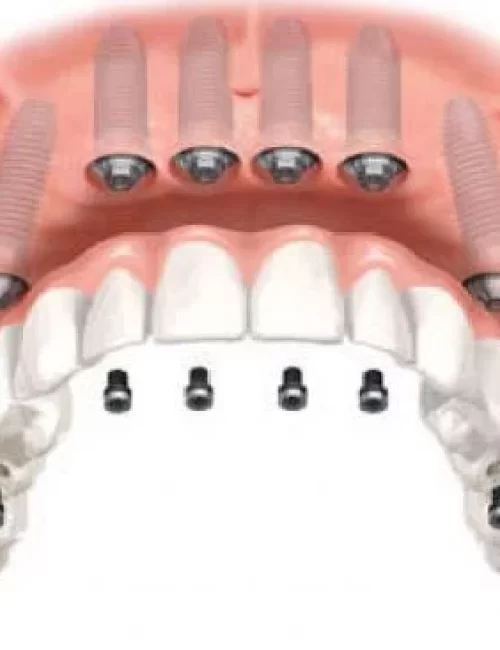

Protesi fisse su impianti

Le protesi fisse su impianti possono essere sostenute da un minimo di 4 impianti ad un massimo di 10 / 12 impianti con una struttura metallica di rinforzo.

Protesi fissa su 4 impianti comprende una intera arcata dentale con una flangia di gengiva (overdentura), ed è una delle alternative più veloci ed economiche per avere di nuovo denti fissi anzichè una dentiera mobile.

Protesi fissa su 6 impianti consiste nell’applicazione di una protesi di 12-14 denti, sorretta da 6 impianti. All on 6 è la tecnica piu innovativa dell’implantologia per ricostruire un’intera arcata con dei denti fissi.